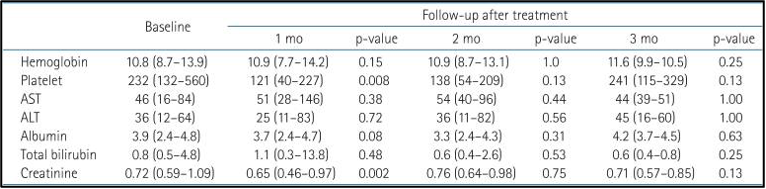

במהלך תקופת הטיפול והמעקב התגלו רעילות בדרגה 3 ומעלה בארבעה מטופלים. שינוי מעבדתי מקו הבסיס בחודש, חודשיים ו-3 חודשים לאחר היפרתרמיה וטיפול קרינתי לכל הכבד (WLI) מוצג בטבלה 2.

להלן טבלה 2: שינוי מעבדתי לאחר טיפול קרינתי לכל הכבד (WLI) והיפרתרמיה